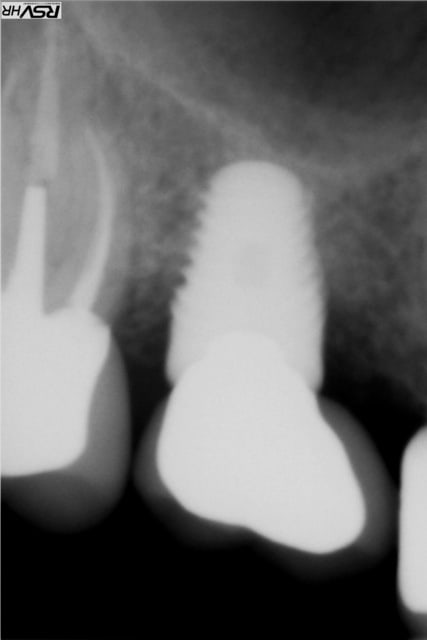

Les délires continuent !(clin d’œil doc Marcus)

37 fêlure-fracture au niveau du plancher en cours de RTE(1er radio avant RTE)

extraction dans la séance forage entre les racines extraction des racines re- forage après dans le septum

pose implant 7 mm long10mm le 11.06.2012

le 25.09.2012 pose d'un faux moignon titane transvissé et

couronne provisoire

RTE en cours sur 36

CCM définitives après

CBCT en 2014 OK pour l'implant